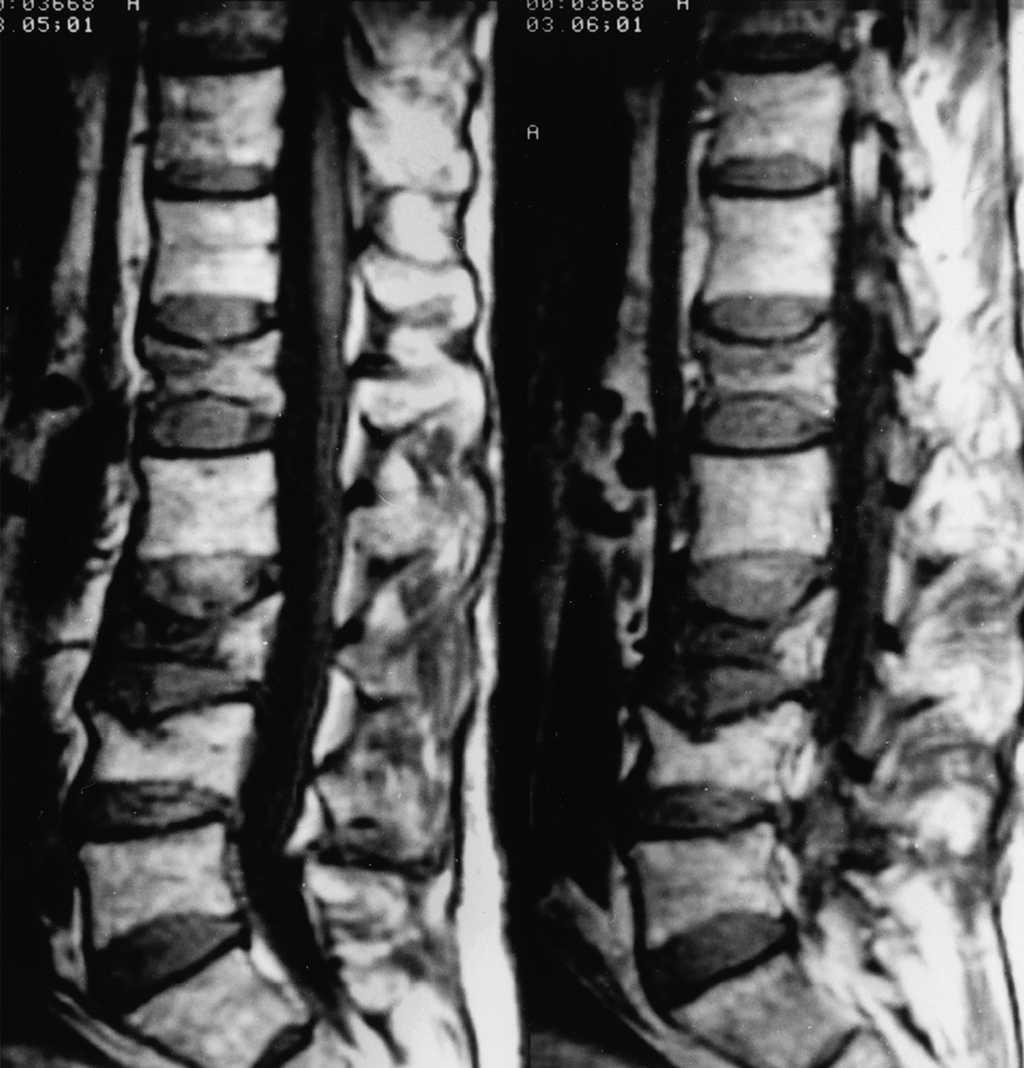

La fractura vertebral por compresión (aplastamiento vertebral) es considerada la fractura osteoporótica más común. Puede causar dolor agudo y/o crónico, aunque a menudo pasa desapercibida y no es diagnosticada. Constituye un factor de riesgo independiente de nuevas fracturas vertebrales y de otras localizaciones, y se asocia a un exceso de mortalidad. En la mayoría de los pacientes, el dolor remite en unas semanas, aunque en un porcentaje de ellos el dolor puede persistir durante más tiempo con discapacidad o incluso requerir ingreso hospitalario para controlar el dolor. FMC, agosto de 2020